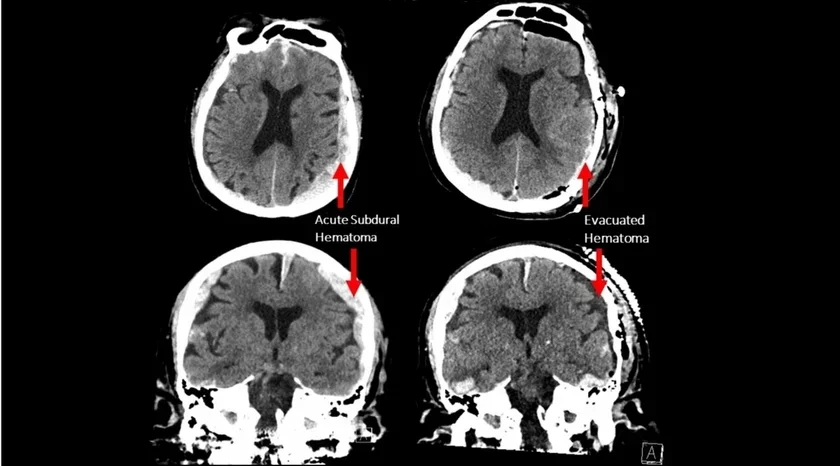

ЭЭГ навукоўцы атрымалі выпадкова пасля таго, як у бальніцу даставілі 87-гадовага мужчыну з эпілепсіяй і траўмай галавы з-за няўдалага падзення. Траўма аказалася цяжкой і выклікала спыненне сэрца, мужчына не выжыў.